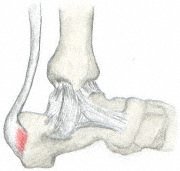

Dolor de talón (Talalgia)

Dolor de talón

El dolor de talón es generalmente resultado de una biomecánica defectuosa (anormalidades en la forma de caminar) que produce demasiada tensión en el hueso del talón y los tejidos blandos unidos a él. La tensión puede resultar de una herida o un moratón sufrido al caminar, correr, o saltar sobre superficies duras; llevar calzado mal construido, o tener exceso de peso.

El hueso del talón es el mayor de los 26 huesos del pie humano, que tiene también 33 articulaciones y una red de más de 100 tendones, músculos y ligamentos. Como todos los huesos, está sujeto a influencias externas que pueden afectar su integridad y su capacidad de mantenernos sobre nuestros pies. El dolor de talón, a veces incapacitante, puede darse en la parte anterior, posterior o inferior del talón.